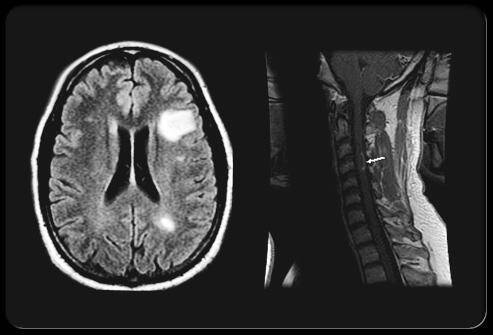

Skleróza multiplex, známá také jako roztroušená skleróza, je závažné autoimunitní onemocnění, při němž imunitní systém napadá ochranný obal nervových vláken (myelin) v mozku a míše. Tento proces, nazývaný demyelinizace, narušuje schopnost nervů přenášet signály.

Výsledkem mohou být velmi rozmanité příznaky – od poruch zraku přes problémy s koordinací až právě po necitelnost, brnění či slabost končetin. Postižené oblasti nervového systému přestávají správně fungovat a části těla mohou reagovat opožděně, nebo dokonce vůbec. I když jde o nevyléčitelné onemocnění, moderní léčba dokáže průběh výrazně zpomalit, a proto je včasné rozpoznání příznaků klíčové.

Necitlivost prstů může vzniknout i tehdy, když je periferní nerv vystaven nadměrnému tlaku. Tento stav se často pojí s chronickou bolestí zad, tzv. lumbagem, nebo s potížemi v oblasti krční páteře (cervikální syndrom). Vyhřezlá ploténka, svalový spasmus či změny na obratlích mohou nerv utlačovat a narušit jeho funkci.

Výsledkem jsou pak různé neurologické projevy – od bolesti vystřelující do končetin až po brnění a ztrátu citu v prstech. Včasná diagnostika (například pomocí zobrazovacích metod) je zásadní, protože dlouhodobý tlak může nerv trvale poškodit a obtíže pak nemusí být plně vratné.